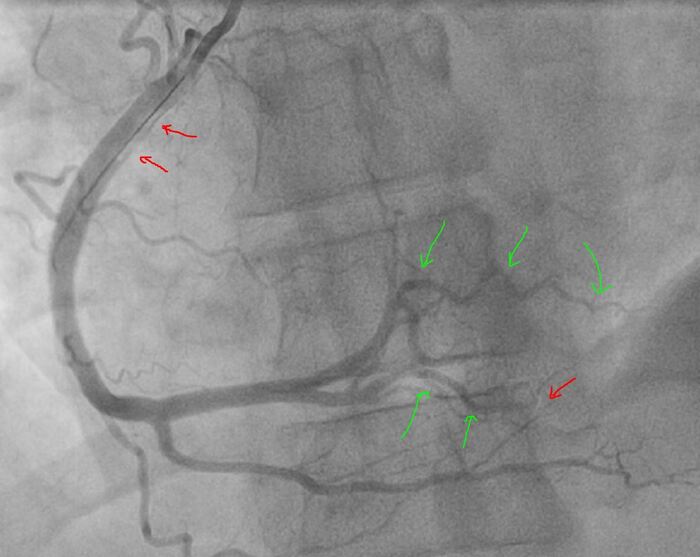

Лечение в рентгеноперационной: пятикратно тромбаспирация (удаление тромба) специальным катетером - удалось полностью удалить тромбы из ЗБВ и частично из ЗМЖВ (Тип аспирата: крупные красные тромбы). Ввиду характера поражения в самой правой артерии (пристеночный тромбоз без значимого стенозирования) решено обойтись без стентирования - начато введение препарата Агграстат (тирофибан) по схеме с продленной инфузией, который избирательно блокирует тромбообразование (блокатор 2Б-3А рецепторов).

Финальный результат: